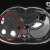

Хирурги больницы Сперанского спасли девочке селезенку, удалив кисту.

Шестилетняя девочка попала в детскую больницу №9 им. Г.Н. Сперанского с большой кистой внутри селезенки.